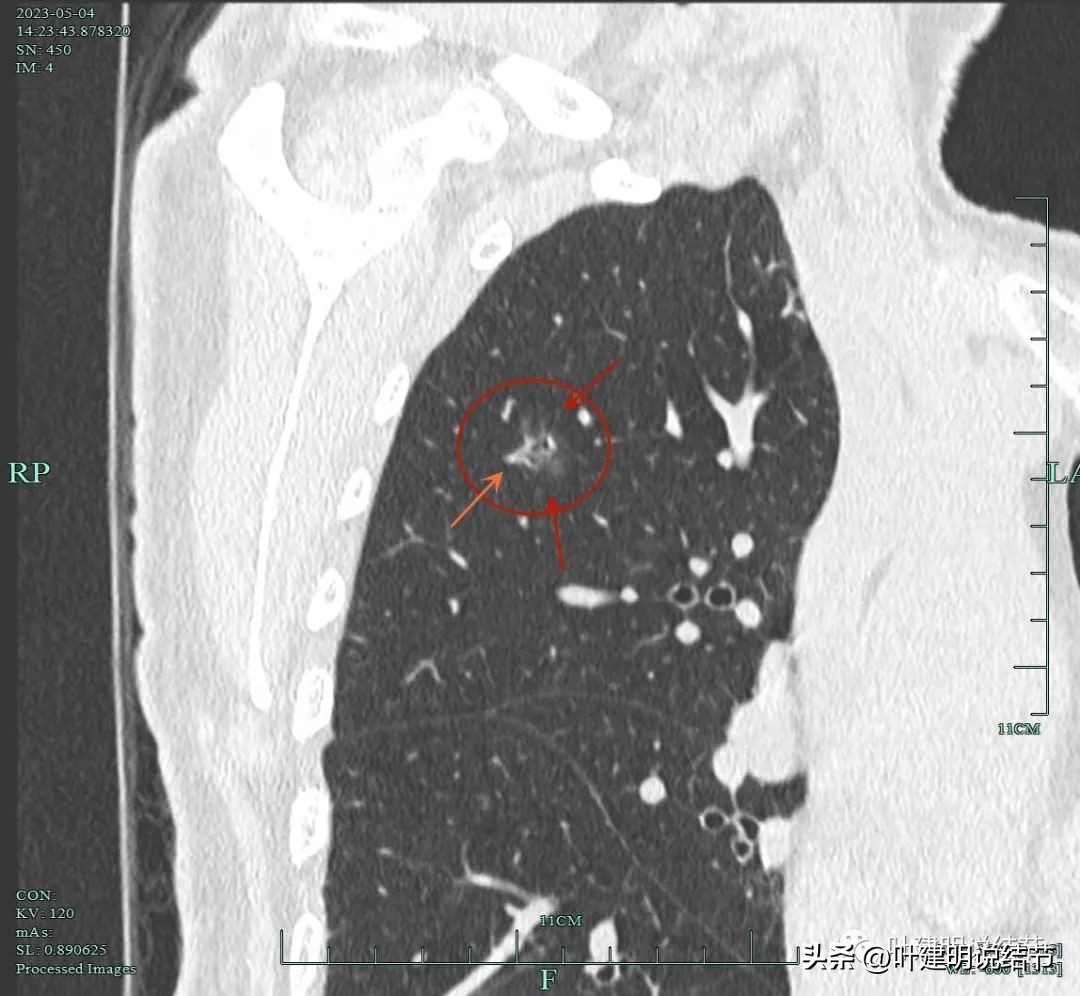

非薄层扫描显露右上叶略显模糊的磨玻璃结节,中间有小空泡的样子,边缘不平显得有毛刺样征,密度不均匀。

薄层显示病灶磨玻璃密度,内部有血管穿行,灶内有小空泡的样子,整体边缘轮廓较清。

灶内穿行的血管有异常增粗,且显得毛糙。灶内空泡样征是扩张的细支气管;表面不平,似有浅分叶的样子。磨玻璃部分密度较低。

上图显示血管进入病灶,进入后似乎就散掉了。

靶扫描重建发现病灶内部穿行血管毛糙,细支气管扩张,边缘毛刺样征。

灶内走行的血管模糊、异常增粗与毛糙。病灶总体轮廓较清,磨玻璃部分密度较低。

上图显示明显的血管弯征。而且磨玻璃病灶密度欠均匀。

病灶分叶、细支气管扩张,微小血管进入;整体轮廓较清。

上图这个视角清楚显示灶内的空泡征是扩张的细支气管。而且灶外细些,灶内更远离肺门,反而扩张,说明病灶有牵拉力呀!

边缘有毛刺征,灶内密度欠均。